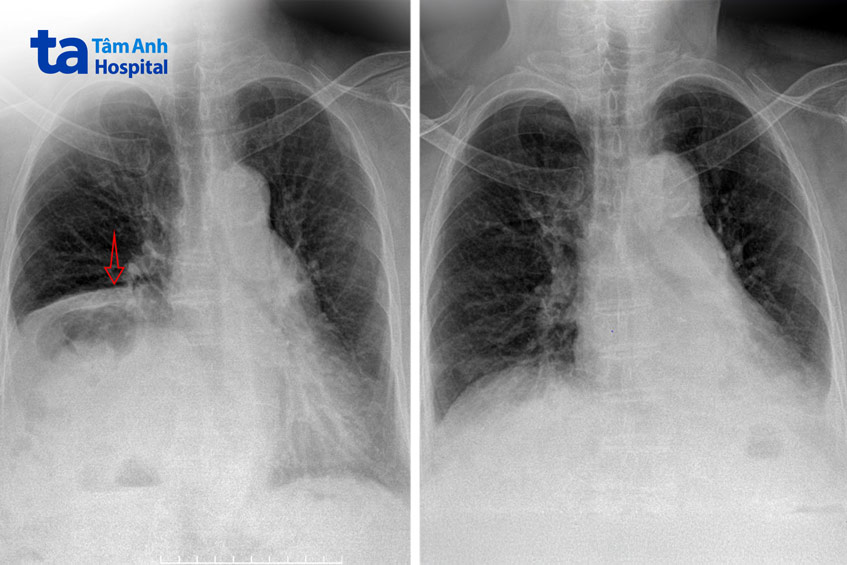

Bác sĩ Khang cho biết hiện nay khâu nếp gấp cơ hoành qua nội soi lồng ngực là phương pháp điều trị hiệu quả nhất. Mục đích của phẫu thuật là làm căng cơ hoành, trả lại thể tích khoang lồng ngực như ban đầu. Ở bệnh nhân này, hình ảnh chụp X-quang sau mổ, cơ hoành phải đã trở về vị trí gần như bình thường.

Bà Điệp ra viện sau mổ 4 ngày, chức năng hô hấp cải thiện rõ, hết khó thở, siêu âm tim kiểm tra áp lực động mạch phổi còn 32 mmHg trở về gần như bình thường. Bà tiếp tục tập vật lý trị liệu, uống thuốc và tái khám theo chỉ định.